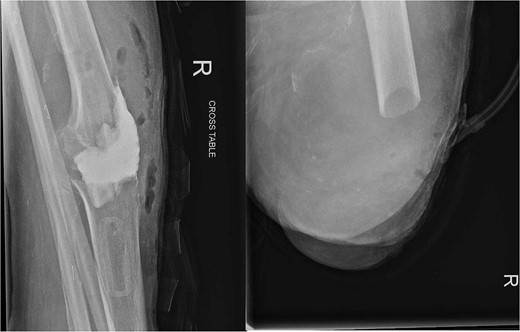

Over the following month, the skin above the fractured patella became necrotic, resulting in an open discharging wound. It was now clear that infection was the issue. With Orthoplastics involvement, she underwent multiple tissue samplings, patellectomy, removal of implants, and insertion of an antibiotic impregnated cement spacer (Fig. 3). Over the ensuing days the infection was uncontrollable despite further debridement and appropriate multi-drug antibiotic therapy. Following a multi-disciplinary team decision, a staged Above Knee Amputation (AKA) was performed (Fig. 3) with negative pressure dressings applied in the interim. Patient was discharged 4 weeks later on achieving closure of the stump. Mobility at discharge was limited to hoist transfers. Unfortunately, the patient passed away 8 weeks later.

On the left X-ray of the knee after removal of prosthesis and insertion of antibiotic-impregnated cement spacer and on the right X-ray of the stump following amputation.